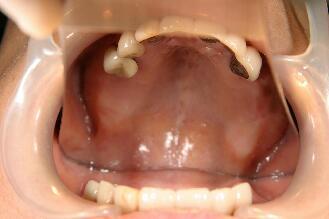

術前の口腔内写真

2ヵ月後の口腔内写真

最終かぶせ物(メタルボンドポーセレン)を装着した口腔内写真